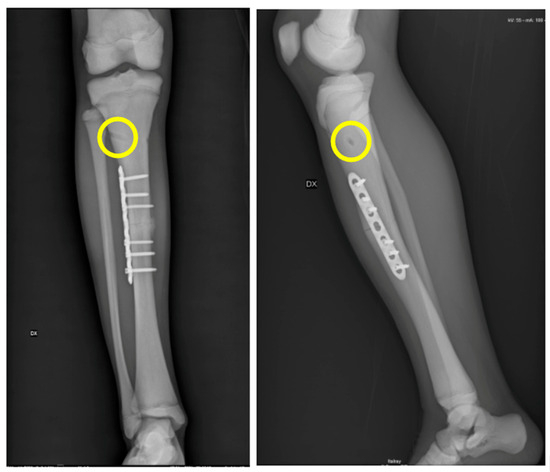

As already specified in the results, not all of the surgeries we referred to were performed at our hospital. However, as much as our experience in treating patients with this condition is relative, by comparing it with what has been reported in the literature, we found many of the difficulties already described [17,18,19,20,21,22]. Intramedullary synthesis in these patients is extremely difficult because of the narrowness of the canal, but also because of the sclerotic nature of the bone, which makes reaming extremely difficult and risky [23,24,25]. In Case 2, we decided to treat the subtrochanteric refracture with previous synthesis removal and intramedullary nail synthesis. However, during canal reaming with progressive burs, the surgery was complicated by an intraoperative fracture that we managed with a cerclage application before proceeding with the long nail placement (Figure 1). In addition, what we found months later during outpatient follow-up was the healing of the refracture foci and, conversely, the nonunion of the iatrogenic fracture. In this specific case, considering the generally poor clinical conditions, we decided not to surgically intervene further.

Figure 1. Case 2 had a subtrochanteric refracture (a,b). During canal reaming, the surgery was complicated by an intraoperative fracture that we managed with a cerclage application before proceeding with the long nail placement (c).